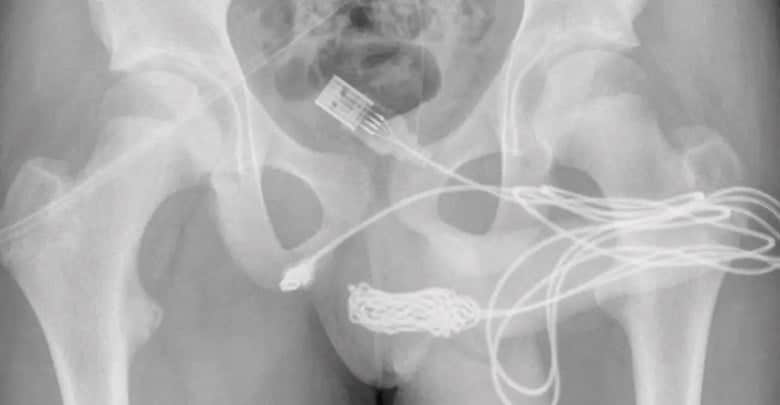

En Londres, Reino Unido, un joven de 15 años quiso hacer un experimento y decidió insertar un cable USB en su pene para medir su longitud; cuando iba a sacarlo no pudo y quiso hacer mucho esfuerzo, lo que ocasionó que el cable se enredara por dentro y terminara en el hospital.

Su caso ha sido detallado en el artículo, titulado «Autoinserción uretral de un cable USB como experimentación sexual: informe de un caso», que se publicó en la revista médica Urology Case Reports junto con las impactantes imágenes.

Tuvieron que cortar el músculo bulboesponjoso, el área entre los genitales y el ano, para sacar el cable USB. Pero no pudieron pasar la parte anudada del cable a través de ese corte antes de sacar las piezas restantes del cable eléctrico. Afortunadamente, el joven no necesitó más tratamiento y fue dado de alta al día siguiente.